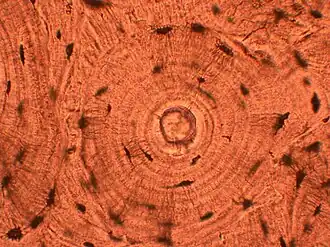

Processing

Water is removed from the sample in successive stages by the use of increasing concentrations of alcohol.[1] Xylene is used in the last dehydration phase instead of alcohol - this is because the wax used in the next stage is soluble in xylene where it is not in alcohol allowing wax to permeate (infiltrate) the specimen.[1] This process is generally automated and done overnight. The wax infiltrated specimen is then transferred to an individual specimen embedding (usually metal) container. Finally, molten wax is introduced around the specimen in the container and cooled to solidification so as to embed it in the wax block.[1] This process is needed to provide a properly oriented sample sturdy enough for obtaining a thin microtome section(s) for the slide.

Once the wax embedded block is finished, sections will be cut from it and usually placed to float on a water bath surface which spreads the section out. This is usually done by hand and is a skilled job (histotechnologist) with the lab personnel making choices about which parts of the specimen microtome wax ribbon to place on slides. A number of slides will usually be prepared from different levels throughout the block. After this the thin section mounted slide is stained and a protective cover slip is mounted on it. For common stains, an automatic process is normally used; but rarely used stains are often done by hand.[1]